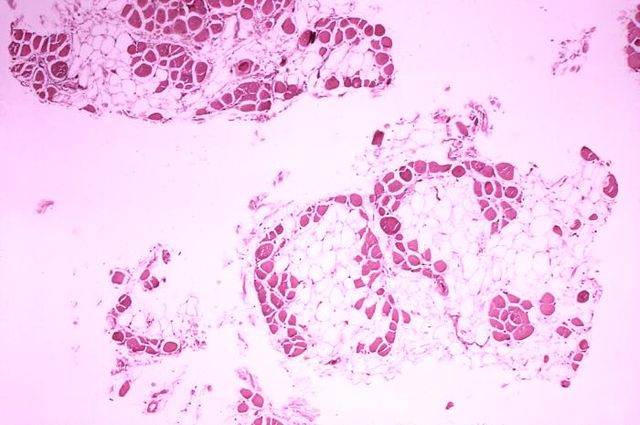

English: Histopathology of gastrocnemius muscle from patient who died of pseudohypertrophic muscular dystrophy, Duchenne type. Cross section of muscle shows extensive replacement of muscle fibers by adipose cells.

Deutsch: Histopathologisches Bild eines Querschnitts aus dem Wadenmuskel (Muskulus gastrocnemius) eines Patienten, der an Muskeldystrophie Typ Duchenne verstarb. Das Bild verdeutlicht, in welchem Ausmaß die (rot gefärbten) Muskelfasern durch Fettzellen (optisch leer = weiß) ersetzt wurden.